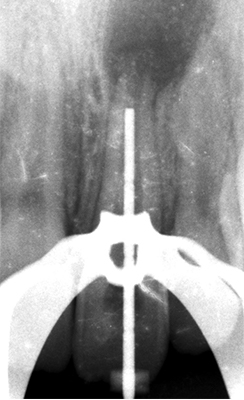

Fig. 02 : radiographie rétro alvéolaire pré opératoire.

Les tests de sensibilités pulpaire sont négatifs. Les tests de percussion et de palpation sont positifs. L’examen radiographique révèle la présence d’une importante lésion péri-apicale ainsi qu’un apex large et ouvert.

La longueur de travail estimée préalablement sur la radiographie pré-opératoire est confirmée à l’aide d’une radiographie lime en place.

Fig. 05 et 06 : détermination de la longueur de travail et radiographie rétro alvéolaire lime en place.